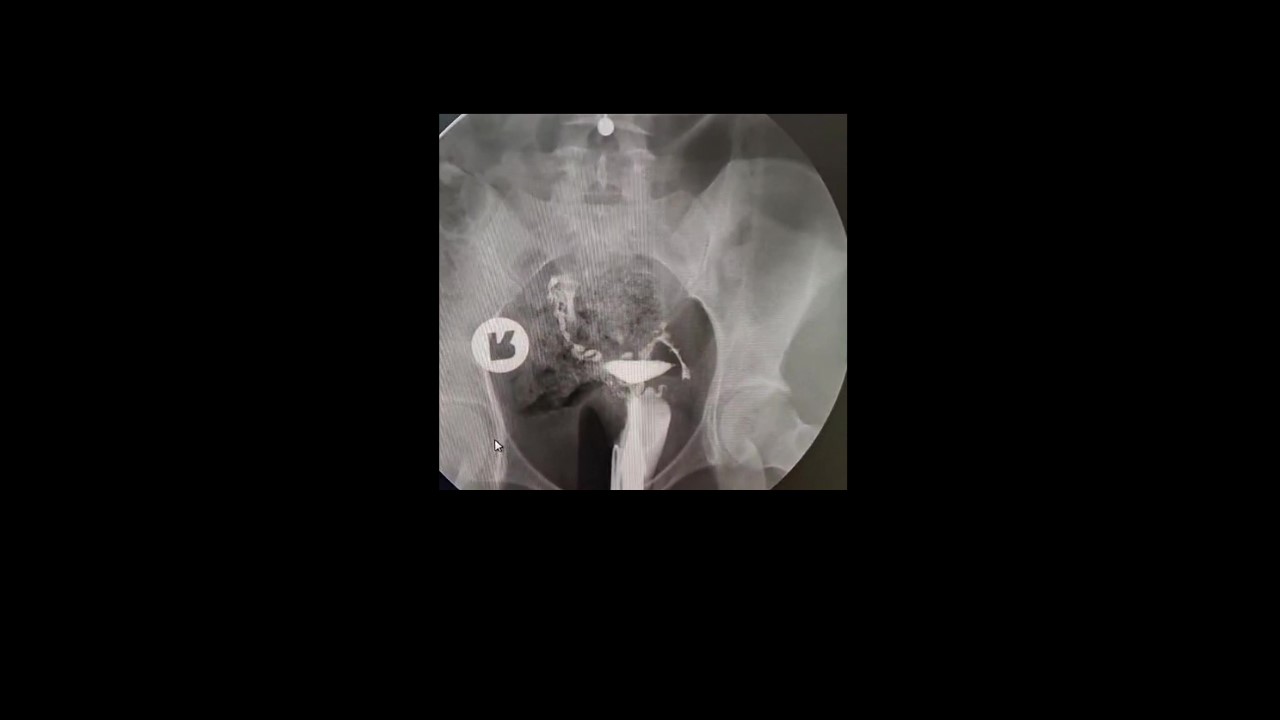

Histerosalpingografi (HSG), rahim ve tüplerin detaylı olarak değerlendirilmesini sağlayan önemli bir görüntüleme yöntemidir. Özellikle çocuk sahibi olmak isteyen kadınlarda tüplerin açık olup olmadığını anlamak için sıklıkla tercih edilir.

HSG temelde tanısal bir yöntem olmakla birlikte, bazı hastalarda tüplerden kontrast maddenin geçişi sırasında oluşan basınç etkisi ile küçük tıkanıklıkların açılabildiği bilinmektedir.

Bu nedenle özellikle açıklığı sınırda olan tüplerde, sadece HSG çekimi sonrasında bile gebelik elde edilebilen hastalar bulunmaktadır. Ancak bu durum her hasta için geçerli değildir ve HSG esas olarak tanı amaçlı bir incelemedir.

Hsg Dinamik bir inceleme olup çekimi yapan hekimin çekim esnasında gerekli manevra ve manipülasyonları yaptırması ve çekim esnasında incelemeyi yapan hekimin dinamik şekilde skopik görüntüleri değerlendirmesi büyük önem taşır. İnceleme sonrasında yapılan HSG incelemesi ile ilgili bir radyolojik rapor yazılması bulguların hem objektif kriterlerle değerlendirilmesine hem de bulguların bir tıbbi doküman haline getirilip takip ve tedavi süreçlerinde katkı sunması için mutlak önem taşır

Rahim iç yapısının değerlendirilmesi, tüplerin açıklığı, kontrast geçişinin özellikleri ve olası patolojilerin doğru şekilde tanımlanması; tedavi planını doğrudan etkiler. Eksik veya yüzeysel raporlar, yanlış yönlendirmelere ve zaman kaybına neden olabilir. Bu nedenle merkezimizde tüm HSG incelemeleri, ayrıntılı açıklamalar içeren ve klinik sürece katkı sağlayan standartlara uygun radyolojik raporlar ile sunulmaktadır.